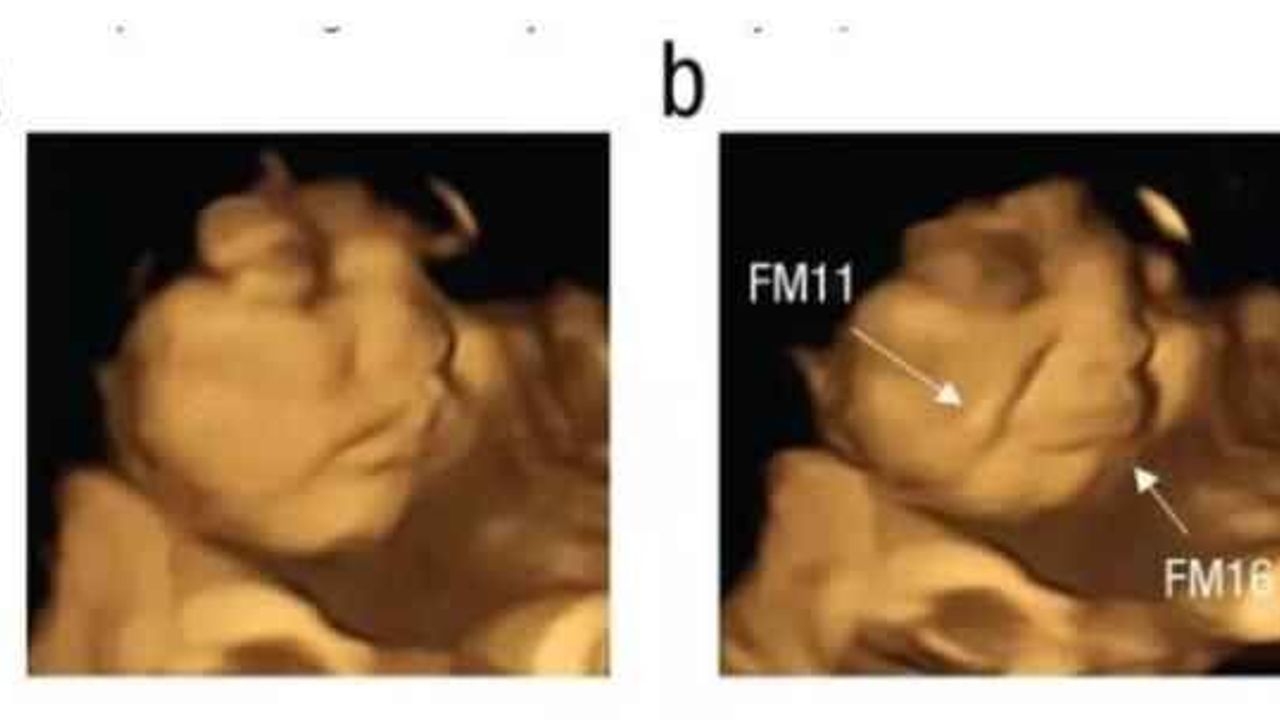

Çalışmaya katılan anne adaylarının raporlama öncesinde herhangi bir gıda tüketmemesi talep edildi. Çalışma kapsamında bir grup anne toz havuç tüketirken diğer grup ise lahana tozu yedi. Lahana tozuna maruz kalan bebeğin, yüzünü ekşittiği görüldü. Fetüslerin reaksiyonunu doğumdan önce gösteren ilk çalışma olarak nitelendirilirken makalede imzası olan Dr. Benoist Schaal da sonuçların bu kadar net olmasını şaşırtıcı olarak değerlendirdi.